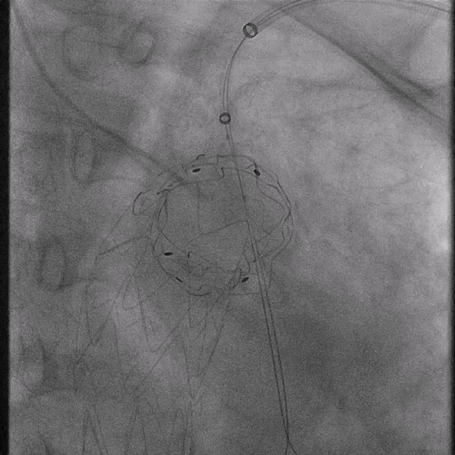

植入华脉泰科覆膜支架

泥鳅导丝怎么用曲乐丰教授团队:0.018"和0.035"普通泥鳅导丝行胸主动脉弓上分支原位开窗的病例分享_https://www.jmylbn.com_新闻资讯_第10张

释放华脉泰科支架前三节,再次造影确认位置

泥鳅导丝怎么用曲乐丰教授团队:0.018"和0.035"普通泥鳅导丝行胸主动脉弓上分支原位开窗的病例分享_https://www.jmylbn.com_新闻资讯_第11张

后释放近端裸支架

泥鳅导丝怎么用曲乐丰教授团队:0.018"和0.035"普通泥鳅导丝行胸主动脉弓上分支原位开窗的病例分享_https://www.jmylbn.com_新闻资讯_第12张

造影确认支架形态